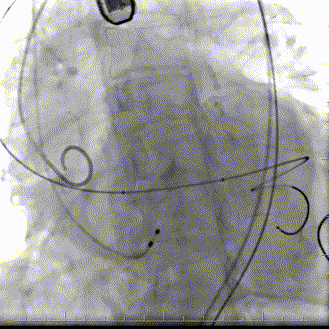

手术过程

患者全麻呼吸插管,TEE,JR4.0造影导管行髂外动脉造影示:髂外动脉弥漫性狭窄,最重70%狭窄。

髂外动脉狭窄

16扩张鞘扩张

沿导丝送入一枚60*120mm高压球囊于狭窄段7atm*120s扩张,AL1、AL2直头导丝跨瓣,测量压力阶差80mmHg,置于超硬导丝到左心。

60x120mm7atm*120s扩张

18m*40mm瓣膜球囊扩张导管,起搏160bpm,行球囊扩张。

18x40mm球囊预扩

同侧Snare协助下成功将TAV21mm微创瓣膜支架系统沿导丝送达主动脉瓣狭窄处,定位满意后起搏160bpm,缓慢释放支架系统。

瓣膜定位

定位释放

完全释放